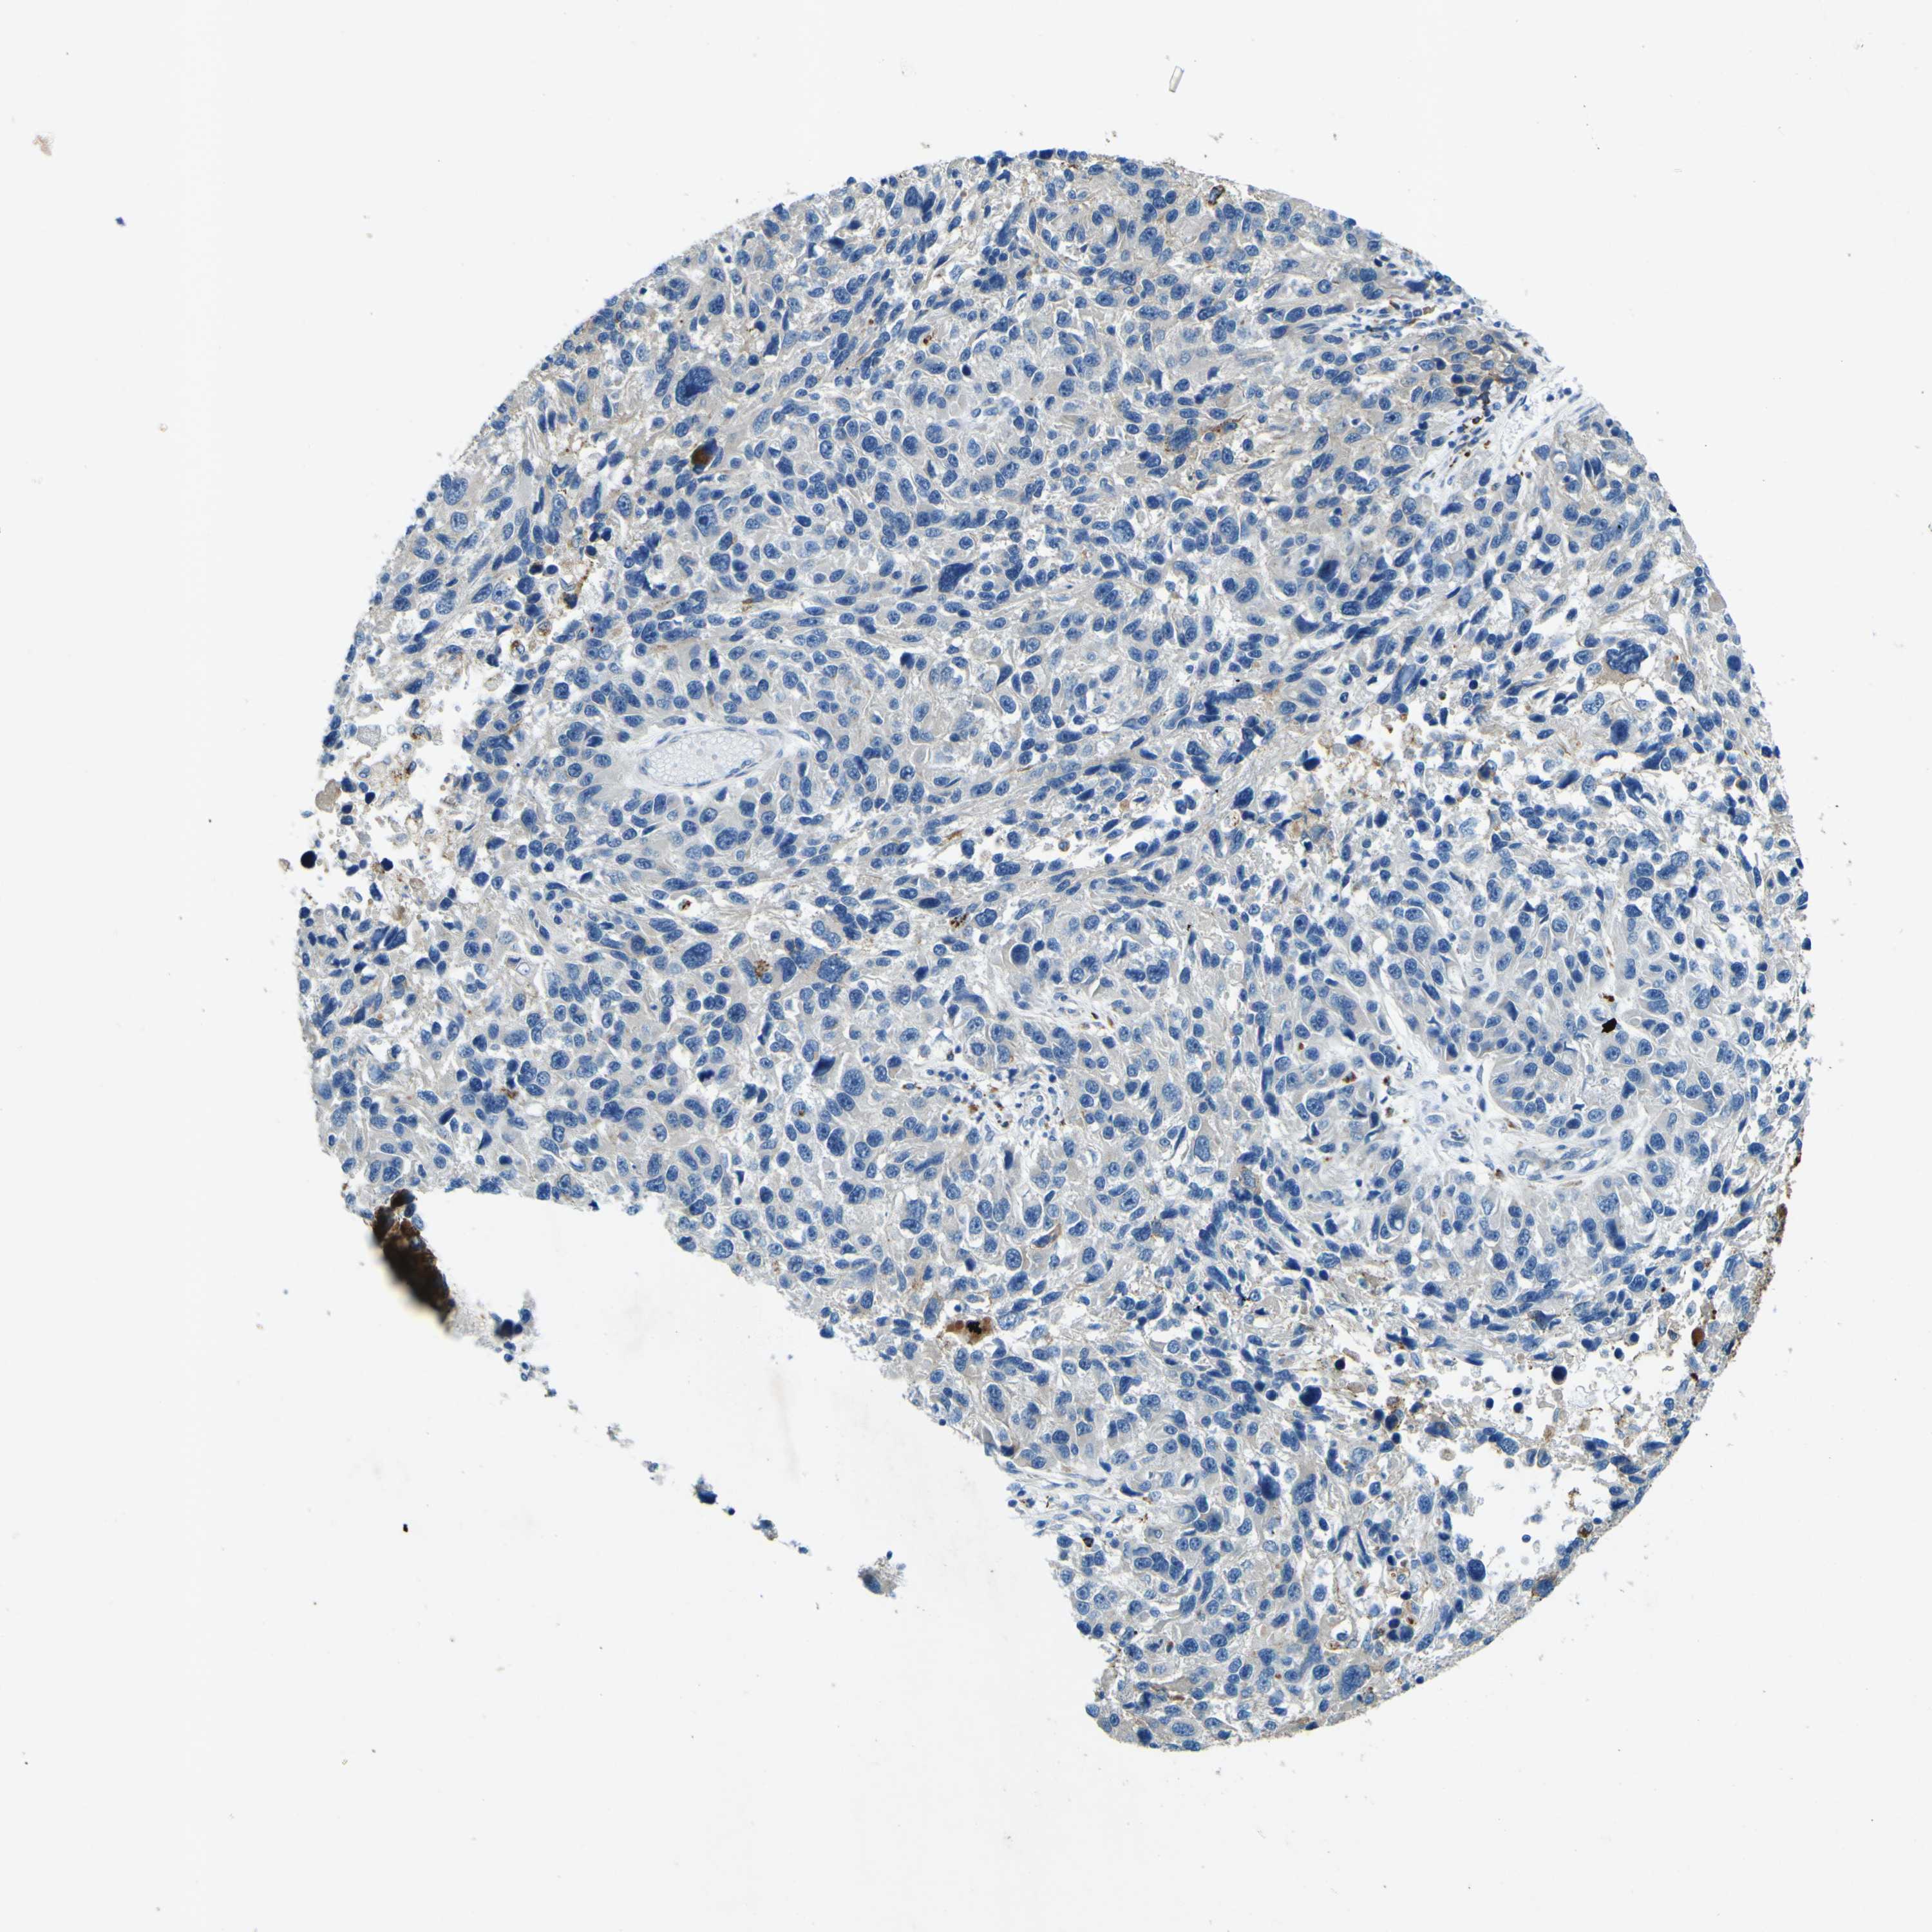

MELANOMA - Protein expressioni

A mouse-over function shows sample information and annotation data. Click on an image to view it in a full screen mode. Samples can be filtered based on level of antibody staining by selecting one or several of the following categories: high, medium, low and not detected. The assay and annotation is described here.

Note that samples used for immunohistochemistry by the Human Protein Atlas do not correspond to samples in the TCGA dataset.

Antibody stainingi

Antibody staining in the annotated cell types in the current human tissue is reported as not detected, low, medium, or high, based on conventional immunohistochemistry profiling in selected tissues. This score is based on the combination of the staining intensity and fraction of stained cells.

Each image is clickable and will lead to virtual microscopy that enables deeper exploration of all samples and also displays staining intensity scores, fraction scores and subcellular localization as well as patient and tissue information for each sample.

Antibody HPA011380

Staining

High

Medium

Low

Not detected

Intensity

Strong

Moderate

Weak

Negative

Quantity

>75%

75%-25%

<25%

None

Location

Nuclear

Cytoplasmic/membranous

Cytoplasmic/membranous,nuclear

Malignant melanoma, NOS

Malignant melanoma, Metastatic site